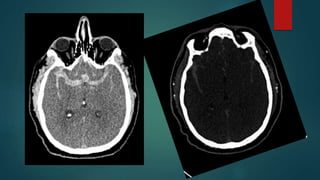

Altered Mental Status